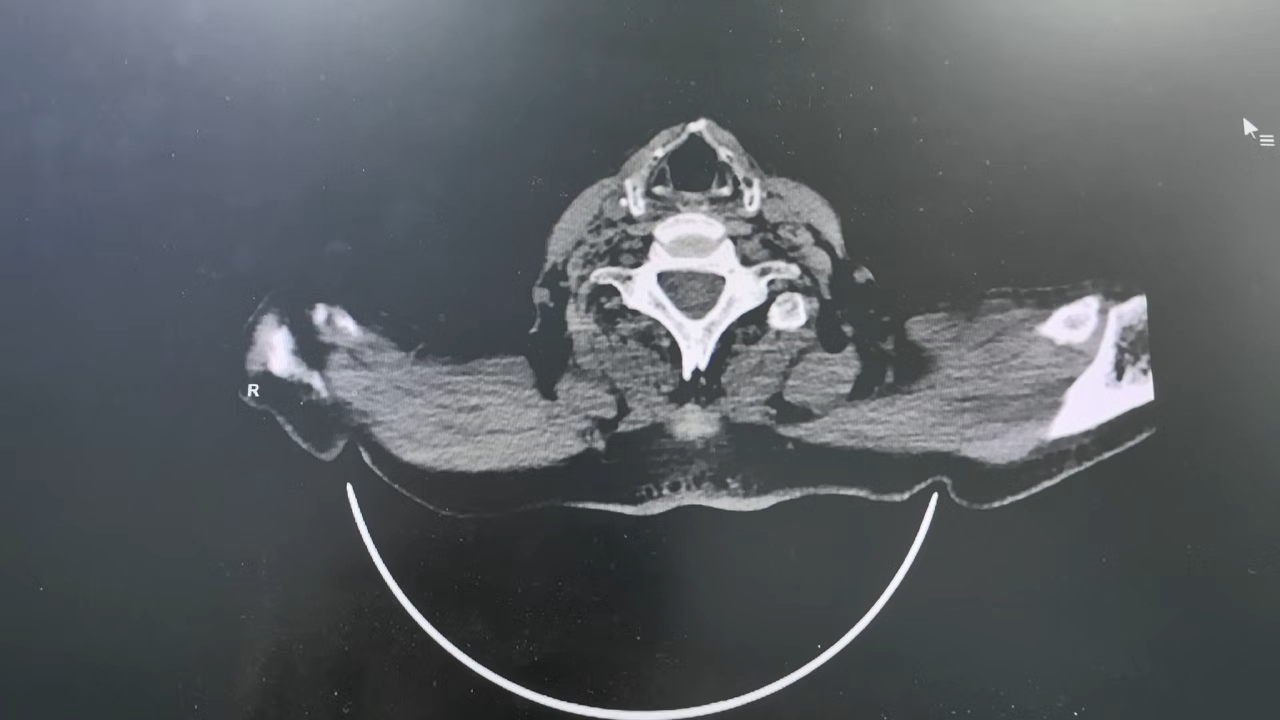

头颅(CT平扫),上腹部(CT平扫),下腹部(CT平扫),盆腔(CT平扫):

双侧基底节区腔隙性脑梗死,必要时MR检查;脑萎缩,脑白质变性;所示部分鼻窦炎;胆囊显示欠清;腹部肠腔多发积气;乙状结肠局部肠壁可疑增厚,建议进一步检查; 膀胱置管中; 前列腺钙化灶; 多发胸腰椎椎体压缩性改变,必要时MR检查; 扫及双侧胸腔少量积液。